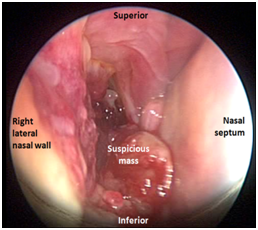

Examination under general anaesthesia confirmed a bulge on the right lateral wall of nose, pushing the middle and inferior turbinates medially. Uncinectomy was performed followed by middle meatal antrostomy on the right side which revealed a globular mass lesion filling the maxillary antrum (Figure 3). The tumor was firm in consistency but no contact bleeding was noticed. At this stage it was decided to carry out the biopsy only. The lesion was confirmed to be a benign schwannoma on histological examination.

Figure 3 Intraoperative view of the right nasal cavity showing a globular mass.